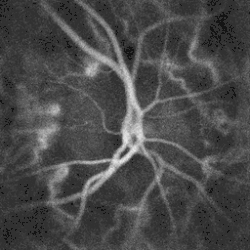

Blood flow in the optic disc revealed by holographic laser Doppler imaging.[4]

Local direction of blood flow with respect to the optical axis revealed by the Doppler spectrum asymmetry in out-of-plane retinal vessels by holographic laser Doppler imaging.[6]

Blood flow in the retina and choroid in the optic disc region can be revealed non invasively by near-infrared laser Doppler imaging.[4] Laser Doppler imaging can enable mapping of the local arterial resistivity index, and the possibility to perform unambiguous identification of retinal arteries and veins on the basis of their systole-diastole variations, and reveal ocular hemodynamics in human eyes.[5] Furthermore, the Doppler spectrum asymmetry reveals the local direction of blood flow with respect to the optical axis. This directional information is overlaid on standard grayscale blood flow images to depict flow in the central artery and vein.[6]